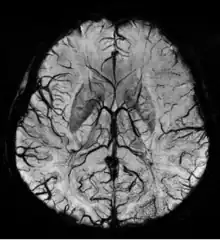

SWI Image acquired at 4 Tesla showing the veins in the brain.

Susceptibility weighted imaging (SWI), originally called BOLD venographic imaging, is an MRI sequence that is exquisitely sensitive to venous blood, hemorrhage and iron storage. SWI uses a fully flow compensated, long echo, gradient recalled echo (GRE) pulse sequence to acquire images. This method exploits the susceptibility differences between tissues and uses the phase image to detect these differences. The magnitude and phase data are combined to produce an enhanced contrast magnitude image. The imaging of venous blood with SWI is a blood-oxygen-level dependent (BOLD) technique which is why it was (and is sometimes still) referred to as BOLD venography. Due to its sensitivity to venous blood SWI is commonly used in traumatic brain injuries (TBI) and for high resolution brain venographies but has many other clinical applications. SWI is offered as a clinical package by Philips and Siemens but can be run on any manufacturer's machine at field strengths of 1.0 T, 1.5 T, 3.0 T and higher.